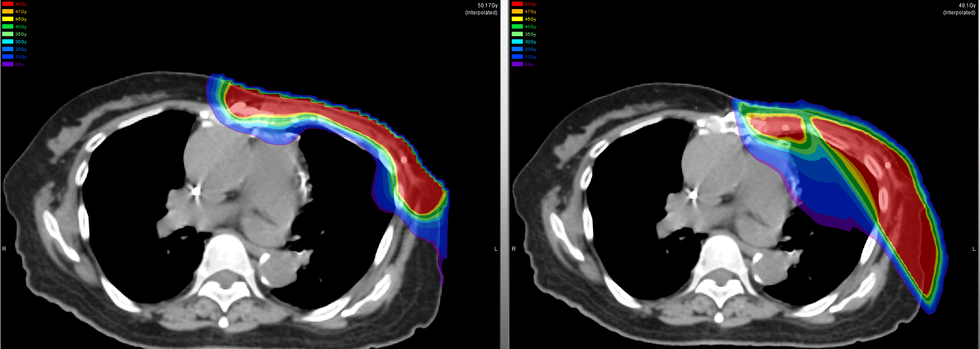

Radioterapia e zvogëlon rrezikun e përsëritjes së sëmundjes (recidivimit) në pjesët e ngelura të gjirit ose në nodet limfatike. Zbatohet, pra për qëllime shërimi - zakonisht pas kirurgjisë kursyese të gjirit (kur nuk hiqet i tërë gjiri) ose pas mastektomisë. Rrezatohen vetëm pjesë të caktuara.

Radioterapia zbatohet çdo ditë (pesë ditë në javë me pushim gjatë vikendit) gjatë 3 javësh ose metoda tjetër është zbatimi çdo të dytën ditë brenda 5 javësh. Një trajtim (fraksion i rrezatimit) zgjat disa minuta dhe nuk jep çrregullime gjatë procedurës.